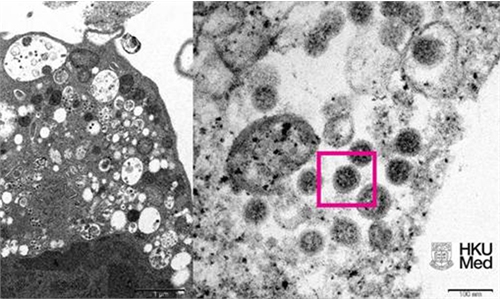

Also on Saturday, Sinovac said that it cooperated with the research team led by professor Qin Chuan, director of the Institute of Laboratory Animal Sciences, Chinese Academy of Medical Sciences & Peking Union Medical College and launched studies on full gene sequencing and work on virus strain isolation. Researches on the mutated variant have been launched as well.

Moreover, with a cooperation agreement signed separately by the company with the research team led by Yuen Kwok-yung from the University of Hong Kong, the samples of the Omicron were delivered to Beijing last Thursday and researches on the variant have been launched at the P3 laboratory of the Institute of Laboratory Animal Sciences, Chinese Academy of Medical Sciences & Peking Union Medical College.

After obtaining the mutant strain, Sinovac can better secure the researches on the cross-neutralization tests of vaccines and the screening of virus strains for vaccines, in a bid to understand the impact of the Omicron variant on existing COVID-19 vaccines and further evaluate the necessity for the development of vaccines against Omicron.